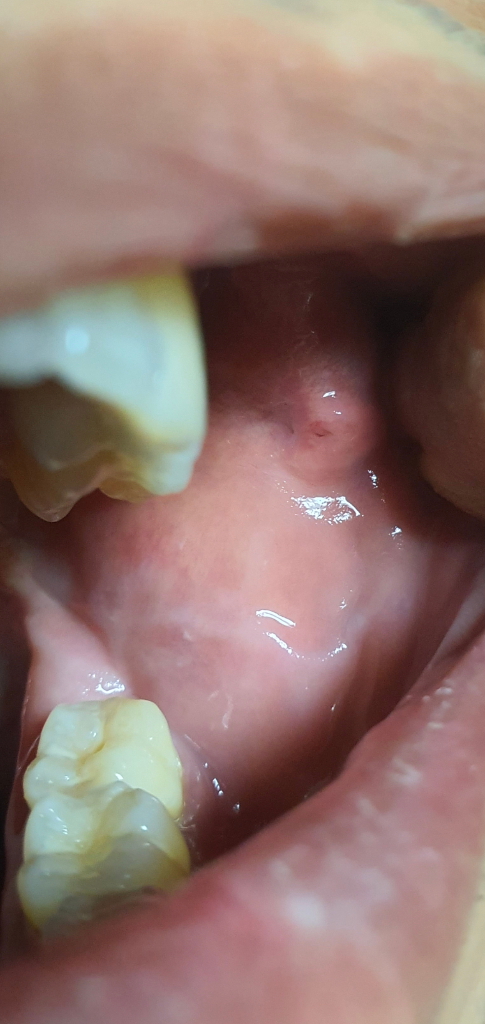

아쉽지만 사진 한 장 가지고 구강암 여부를 구체적으로 감별할 수는 없습니다. 관련하여서는 이상 소견이긴 한 만큼 이비인후과적으로 진료 및 정밀 검사를 한번 받아보시길 권고드립니다.

안녕하세요. 서민석 의사입니다.

사진으로만 보기는 어려울 것 같아요. 직접 목 안을 봐야 병변이 이상한지 확인이 가능합니다. 이비인후과에서 진료를 받으시기 바랍니다. 어쨌든 비정상적으로 튀어나와 있고, 없어지지 않는 경우라면 구강암 가능성도 고려해야 하구요.